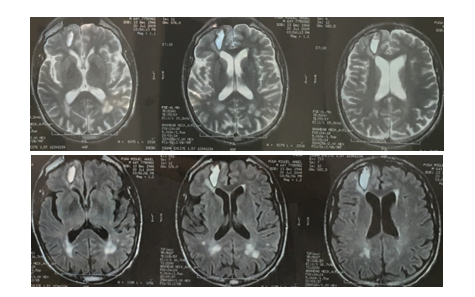

A 71-year-old man was assessed in 2016 at the emergency department due to alert deterioration caused by dehydration, his past medical history was remarkable. He had suffered from recurrent lobar hemorrhagic stroke since age 65. 2009 (right frontal), 2013 (left temporal) (Image 1), leading to an amyloid angiopathy diagnosis base on Boston Criteria; during 6 months in 2012 a low dose of oral prednisone was administered due to a suspicion of inflammatory amyloid angiopathy. After fluid administration the patient recovered to his baseline status: a major cognitive deterioration, left hemiparesis and severe mix aphasia was observed as sequelae, he was able to walk supervised. His relatives reported a gradual cognitive deterioration during the past year.

Image 1 Image 1 A) Axial MRI T2 and FLAIR. Right frontal hematoma. Subcortical white matter lesion (2009). B) CT Scan. Axial. Left temporal hematoma. (2013)